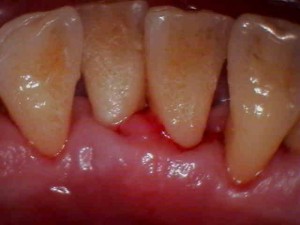

治療前の歯ぐき

歯ぐきが赤く腫れています